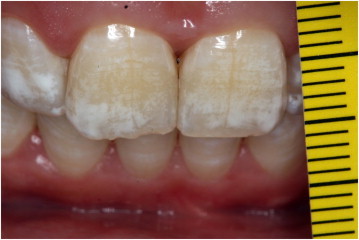

Too much of what causes this?

Fluoride (esp. in the first few years of life when these teeth are developing)

What’s happening here?

Fluorosis from too much fluoride exposure